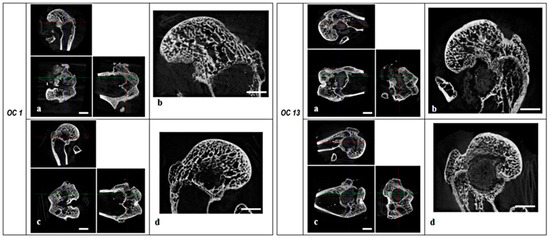

2.1.2. Microtomography

2.2.2. Microtomography